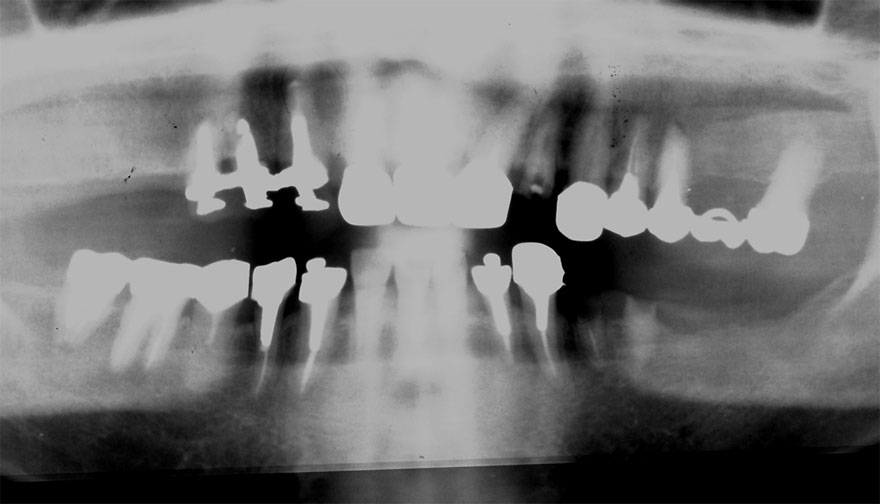

初診時 41歳 男性 平均歯槽骨喪失量:4.11mm

30年後 71歳

平均歯槽骨喪失量:3.70mm

30年間再生量:+0.41mm

年間再生速度:+0.014mm

(ケア頻度:1.27ヵ月ごと)